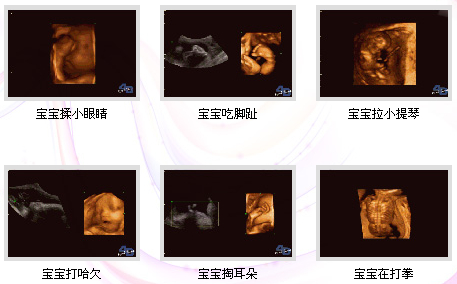

四維彩超簡稱"4D",也就是四維成像技術(shù),是目前上較為先進(jìn)的超聲診斷技術(shù),能直觀、立體顯示人體器官的三維結(jié)構(gòu)及動態(tài)、實時地觀察立體 結(jié)構(gòu),廣泛運用于對胎兒進(jìn)行超聲檢查,立體觀察宮內(nèi)胎兒發(fā)育情況的同時,還能清晰顯示胎兒在宮內(nèi)的動態(tài),讓準(zhǔn)爸爸準(zhǔn)媽媽一起觀看寶寶在媽媽肚子里的各種動 作神態(tài),另外還能制作成光盤,讓寶寶擁有較完整的0歲相冊,留下的記憶。 >>>>看文章太累?直接聯(lián)系在線產(chǎn)科醫(yī)生

作為準(zhǔn)媽媽的你,擁有一個健康的寶寶是你的要求。莆田盛興醫(yī)院引進(jìn)的美囯GE四維彩超設(shè)備,就是為了準(zhǔn)媽媽擁有健康的寶寶而提供的科學(xué)保 障。準(zhǔn)媽媽們通過四維彩超,不僅可以看到宮內(nèi)胎兒打哈欠、伸懶腰、吮手指等等好看的動作,還能夠多方位、多角度觀察宮內(nèi)胎兒的生長發(fā)育情況,為早期診斷胎 兒先天性體表畸形、先天性心臟疾病提供準(zhǔn)確的科學(xué)依據(jù),并可以直觀的觀測胎兒實時動態(tài)活動圖像。

四維彩超視頻是什么樣子的?

莆田盛興醫(yī)院產(chǎn)科醫(yī)生:四維彩超能多方位、多角度地觀察宮內(nèi)胎兒的生長發(fā)育情況,為早期診斷胎兒先天性體表畸形和先天性心臟疾病提供準(zhǔn)確的科學(xué)依據(jù)。四維彩超圖像清晰,可將寶寶的樣子和動作制作成照片或DVD,讓寶寶擁有較完整的0歲寫真。